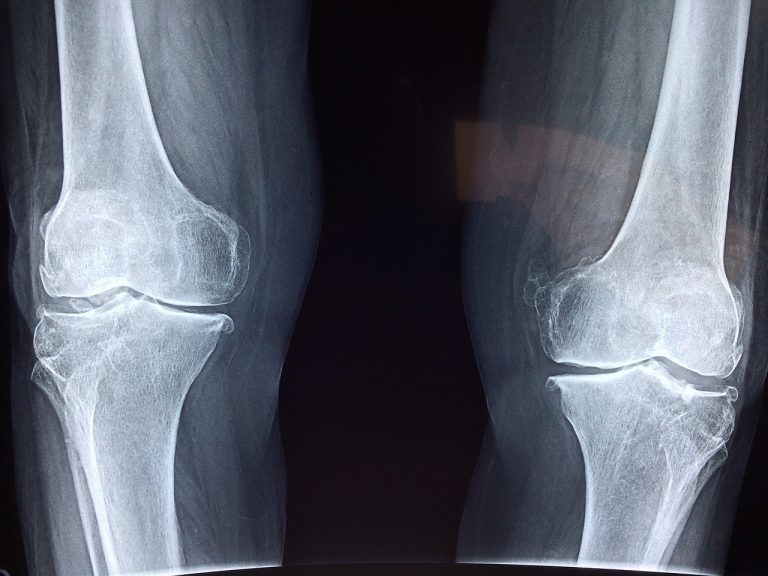

An xray showing bone disorders like osteoporosis.

Osteoporosis and Osteopenia: Osteoporosis is a condition where bones lose mineral density, increasing the risk that they may fracture. Osteopenia is the term for when bones have lost some mineral density but to a lesser extent than in osteoporosis. Treatment of osteoporosis or osteopenia includes evaluating for underlying causes of bone loss and then developing a plan of care to address these causes, use of medications when appropriate to reduce the risk of fracture, and lifestyle interventions that can help maintain or improve bone density.